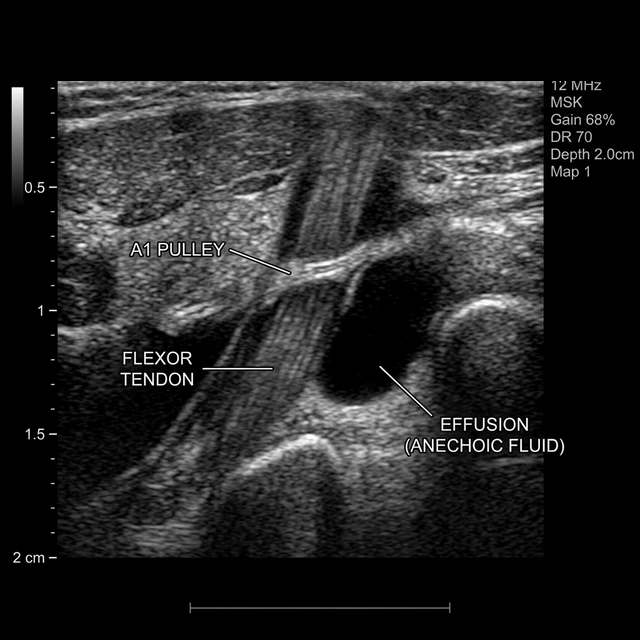

Your fingers move because tendons (like strings on a puppet) connect the muscles in your forearm to the bones in your hand. These tendons glide smoothly through protective tunnels known as tendon sheaths. In Trigger Finger, the tendon or the A1 pulley (a ring of tissue holding the tendon in place) becomes inflamed and thickened.

As the tendon swells, it forms a small nodule. When you bend your finger, this nodule struggles to pass through the narrowed pulley. It eventually pops through with a painful “catch.” When you try to straighten the finger, the nodule gets stuck on the other side, locking the finger in a bent position until it snaps back—hence the name “trigger” finger.

At LSRI, Dr Prashant Sankaye exclusively utilises high-frequency diagnostic ultrasound to guide every single trigger finger injection in real-time. This is the gold standard of modern MSK care.

• Identify the Exact Pathology: Confirming the precise location and severity of the tendon thickening before the needle even touches the skin.

• Guarantee Perfect Placement: Navigating the needle with millimetre precision directly into the microscopic space of the tendon sheath, ensuring 100% of the medication reaches the target.

• Avoid Complications: Completely avoiding an accidental injection into the actual tendon tissue or nearby digital nerves.